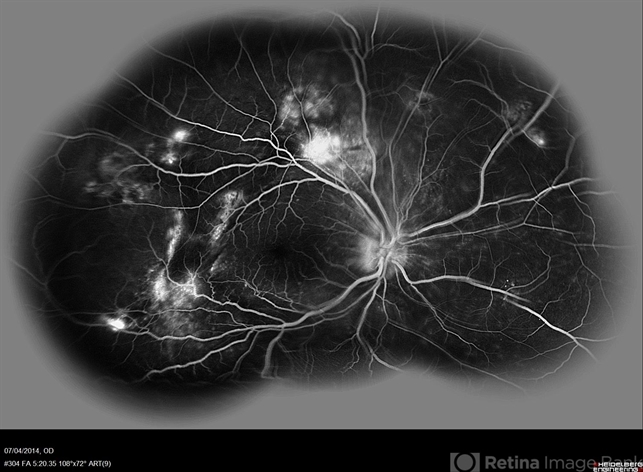

- multifocal central serous chorioretinopathy (CSCR)

Scanning laser ophthalmoscope

Heidelberg HRA + OCT Spectralis - Description

- FA (composite Image) a 38-year-old man with multifocal CSR and inferior exudative retinal detachment on both eyes (Harada Syndrome).